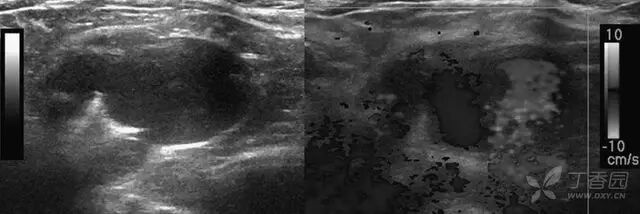

图 2 颈部横断面灰阶和彩色多普勒声像图显示一分叶状薄壁囊性结构,内见血流信号